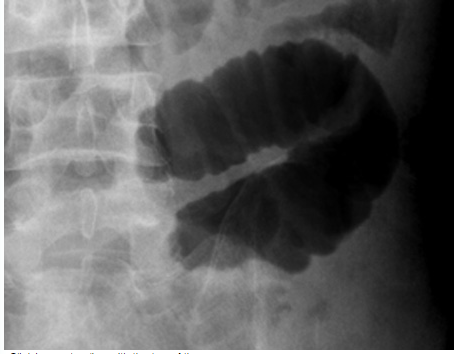

What does this X-ray show

A

Large bowel obstruction

Note

• dilation of the caecem >9cm is abnormal

• dilation of any other part of the colon >6cm is abnormal

• abdominal X-ray may demonstrate the level of obstruction

• abdominal x-ray cannot reliable differentiate mechanical obstruction from psuedo-obstruction

X-ray

• colon is dilated down to the level of the distal colon

• Soft tissue density at level of obstruction

• small volumen of gas has reached the rectum (obstruction no definite)